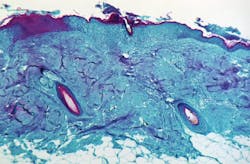

Monkeypox is a rare but potentially serious viral illness that typically begins with flu-like illness and swelling of the lymph nodes and progresses to a widespread rash on the face and body. Most infections last 2-4 weeks. Monkeypox is in the same family of viruses as smallpox but causes a milder infection. In this case, laboratory testing at CDC showed the patient is infected with a strain of monkeypox most commonly seen in parts of West Africa, including Nigeria. Infections with this strain of monkeypox are fatal in about 1 in 100 people. However, rates can be higher in people who have weakened immune systems.